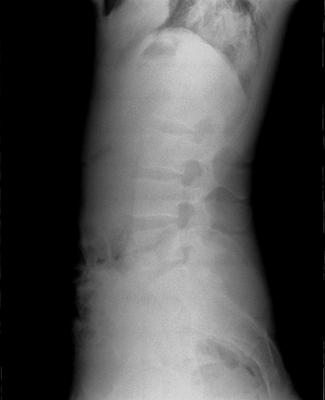

LAT Lumbar

Hey! My name is Kiko and I am an x-ray tech at a chiropractic practice. I have a fusion of my transverse processes of my L5 to S1, and I was looking for another set of eyes on it. I practice yoga and I notice that any forward folds and back-bends cause a lot of pain. I also have extremely tight hamstrings, which I'm sure contribute to the pain. I was just wondering if you guys could look over these and give me some detailed analysis.

Certainly you have a transitional segment at the the lumbosacral junction. S1 has a large spatulated transverse process on the left which appears to articulate with the sacrum - you can see the sclerosis. I don't see any fusion to the SI. The facets are difficult to visualise. Rudimentary ribs at L1 as is common with a lumbarisation of S1.

Also a very small pincer deformity in the left hip; any groin pain or stiffness?

I'd also be looking for abnormal motion palpation findings at L2 and L3.